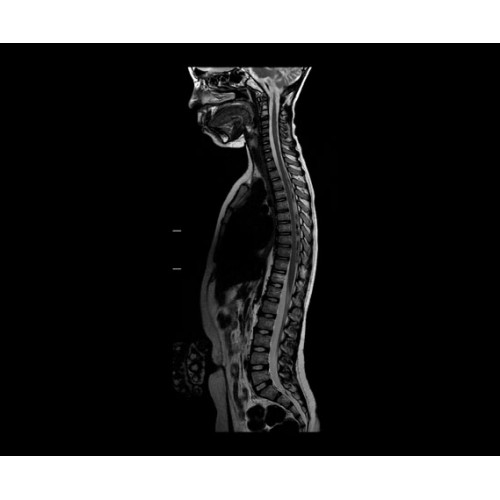

Кроме того, в результате использования технологии TOF и инновационной технологии реконструкции Q.Clear вы сможете добиться прекрасного соотношения сигнал/шум. А благодаря технологии нулевого времени эхо (ZTE) визуализировать костную структуру без ионизирующего излучения. Все эти разработки для улучшения качества сканирования и точности анализа помогут вам использовать весь потенциал ПЭТ/МРТ.

• МРТ с функцией нулевого времени эхо (ZTE) отличается точностью, возможностью персональных настроек и отсутствием ионизирующего излучения. Она приходит на смену традиционному исследованию на основе рентгеновского излучения. МРТ с функцией нулевого времени эхо (ZTE) на базе SIGNA ПЭТ/МРТ является более надежной и быстрой по сравнению с системами, использующими сверхмалое время эхо (UTE).